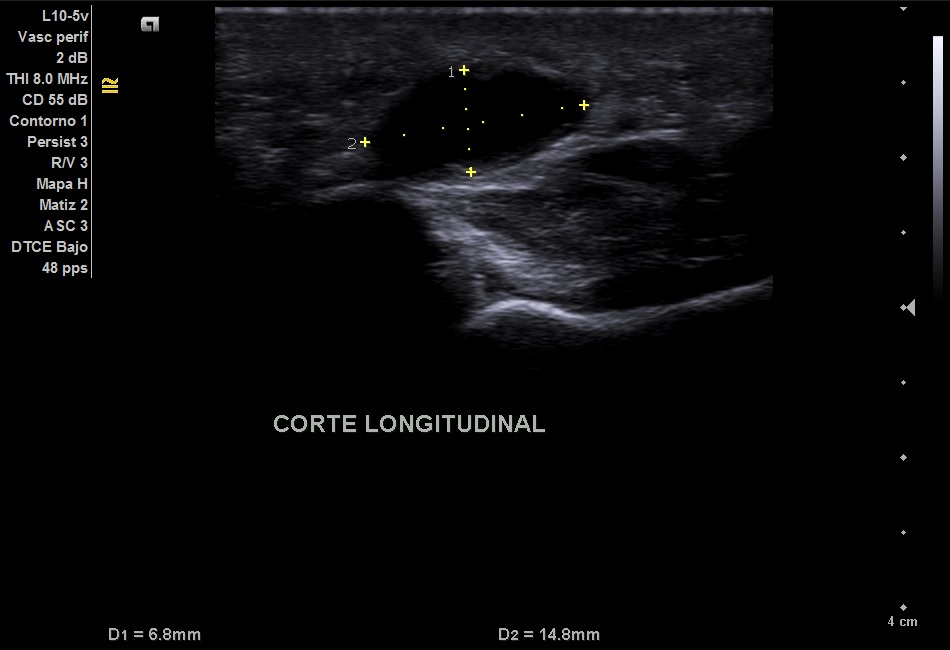

Imagen 1: Corte longitudinal del aneurisma

Imagen hipoecoica de 6,8 x 14,8 mm.